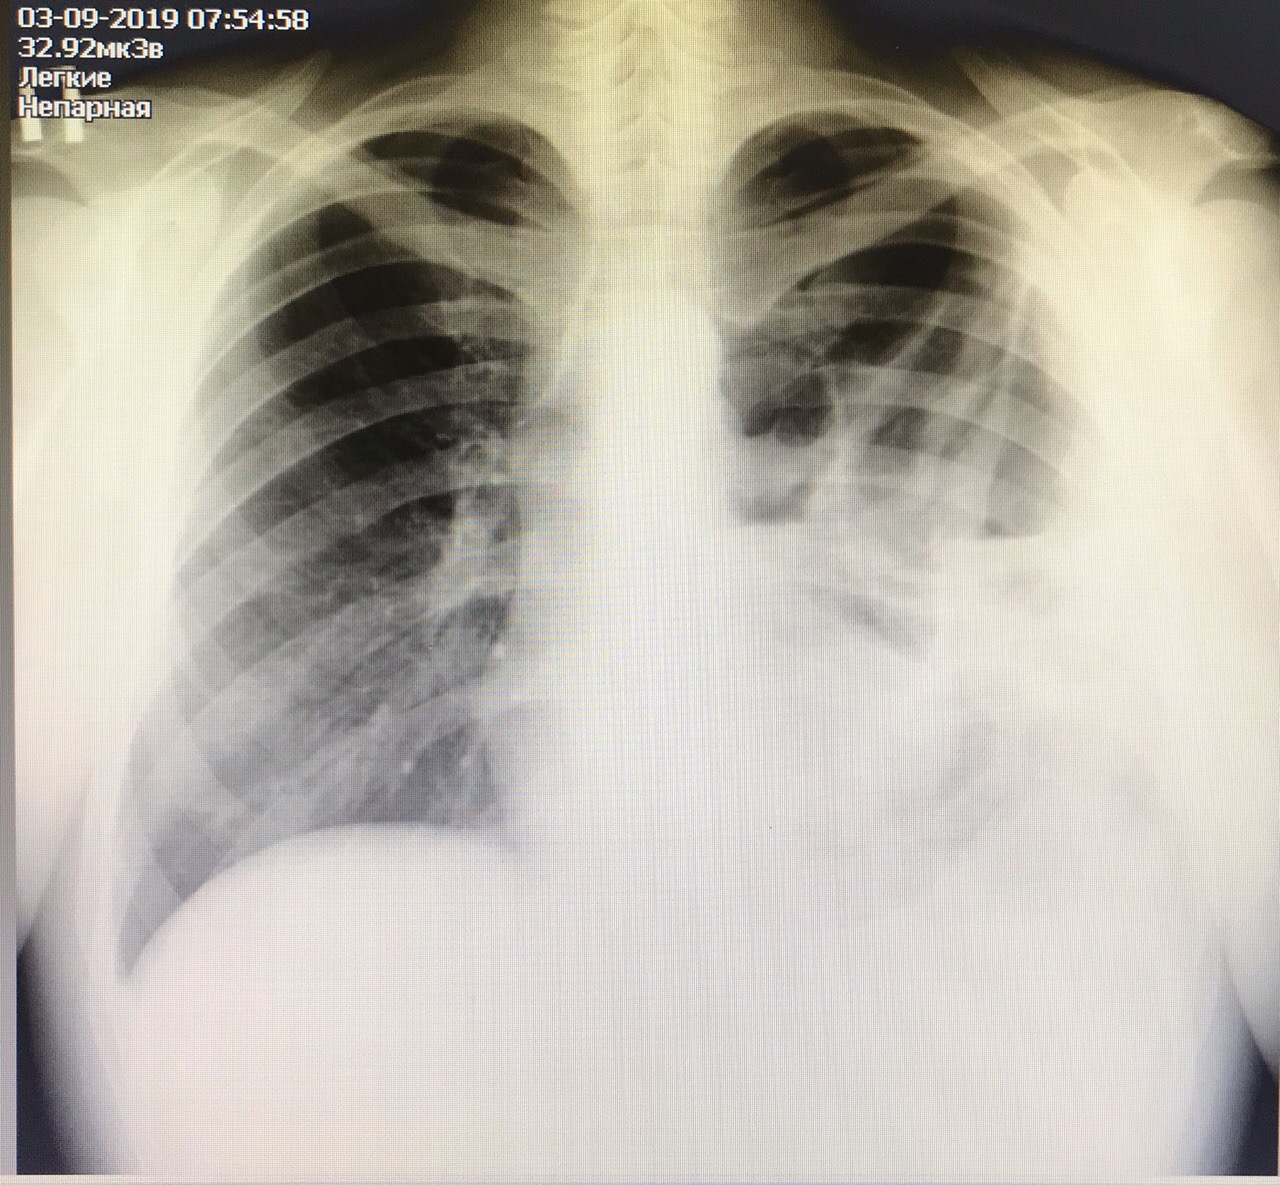

Гидроторакс. Серия снимков.

1 - лежа. Так делать не надо! Надо только сидя!

2 - сидя. Понятно, что гидроторакс за раз не победить

3 - удалено 1100.

4 - удалено ещё 1200. И диуретики все эти дни.

Обсуждалось в ГОспитале Ослабленных Сердец.